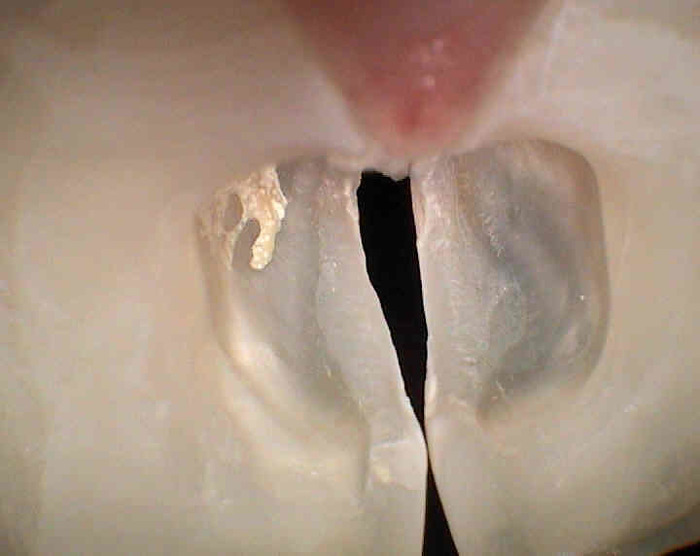

Úvod > Informace > Skryté zubní kazy > Skryté zubní kazy zubů 11 a 21